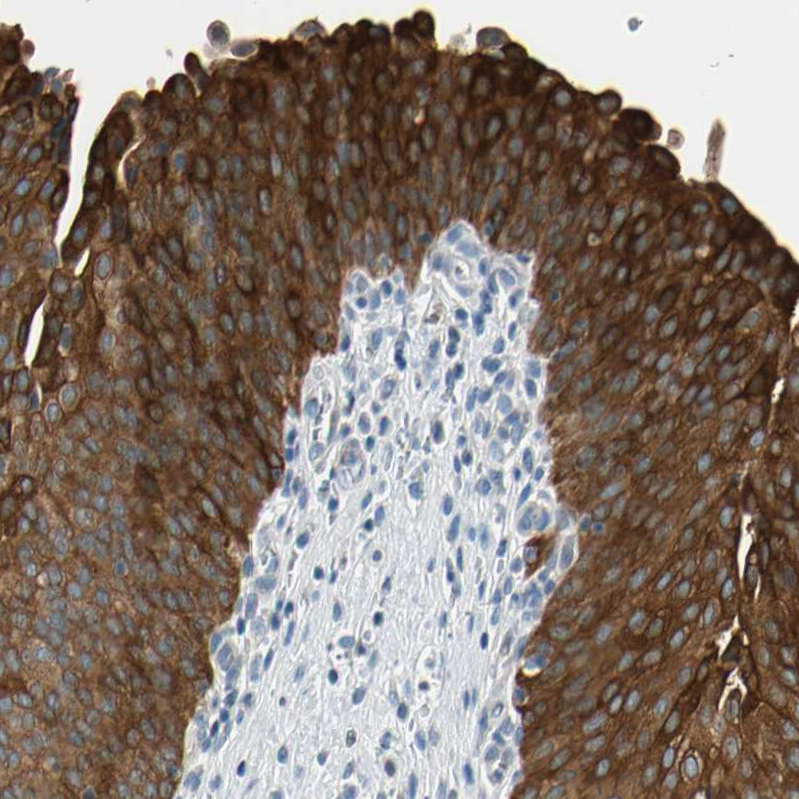

Immunohistochemical staining of human urinary bladder shows strong cytoplasmic positivity in urothelial cells.